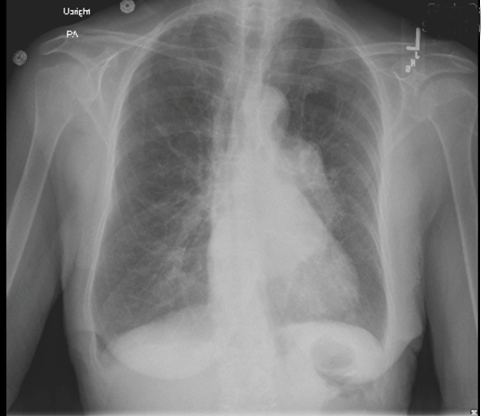

Figure 1: Chest X-ray demonstrating a large mass in the left posterior mediastinum.